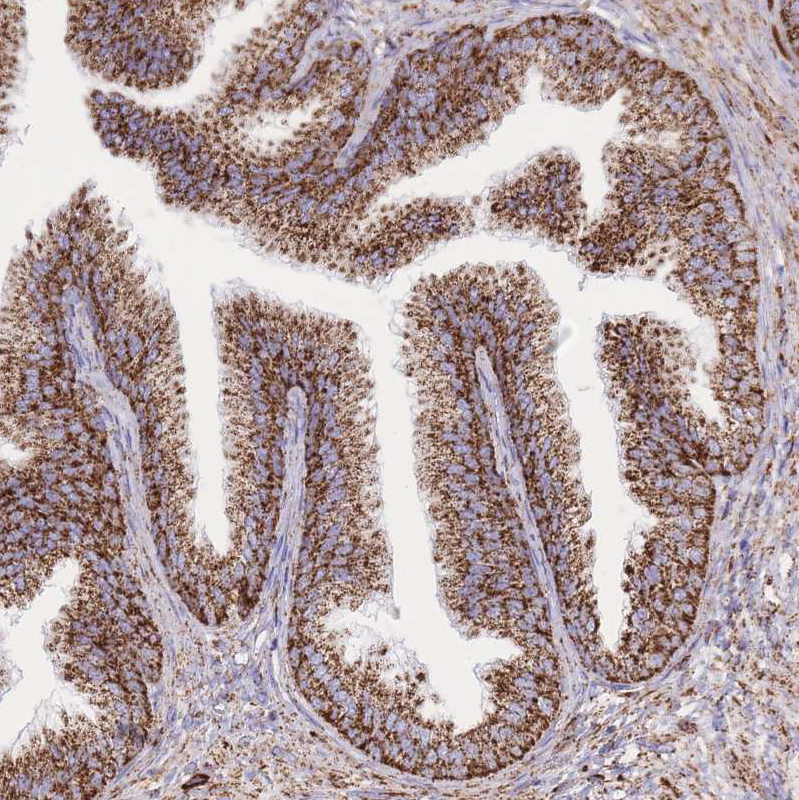

Immunohistochemical staining of human Liver shows strong granular cytoplasmic positivity in hepatocytes.